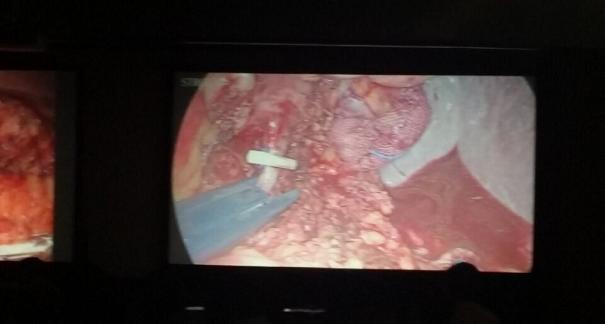

2015年10月23-25日,河北省醫(yī)學(xué)會(huì)肝膽外科學(xué)術(shù)年會(huì)在河北省石家莊市頤園賓館隆重召開。本次學(xué)術(shù)會(huì)議河北省醫(yī)學(xué)會(huì)特邀了北京301總院的胡明根教授、天津第一中心醫(yī)院的張雅敏教授、山西醫(yī)大醫(yī)院的趙浩亮、河北醫(yī)科大學(xué)第二醫(yī)院劉建華教授等國內(nèi)知名專家參會(huì)。參加會(huì)議的醫(yī)院達(dá)100余家,近300名肝膽外科的臨床專家和一線醫(yī)生們親臨會(huì)場,在此進(jìn)行廣泛的學(xué)術(shù)交流。25號(hào)全天會(huì)議安排了五臺(tái)手術(shù)視頻演示,全體參會(huì)人員進(jìn)行觀摩,并實(shí)時(shí)提問,進(jìn)行手術(shù)交流。演示手術(shù)包括腹腔鏡胰、十二指腸切除術(shù)、腹腔鏡左、右半肝切除術(shù)、腹腔鏡門脈高壓癥的治療、兩鏡或三鏡聯(lián)合膽石癥的治療、開腹胰、十二指腸切除術(shù)、手術(shù)演示中多次使用了我公司產(chǎn)品速豐(可吸收止血結(jié)扎夾),產(chǎn)品使用滿意度受到專家們的一致好評(píng)。